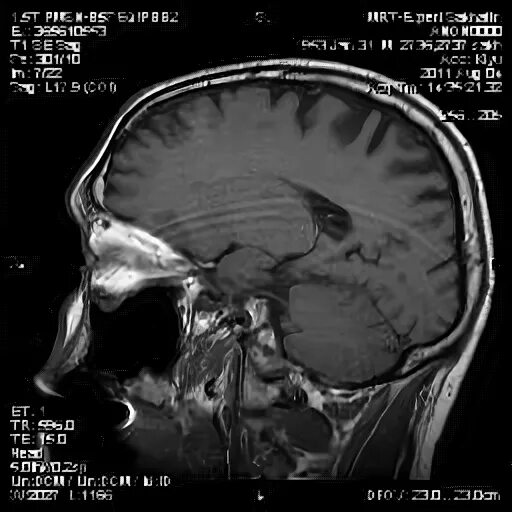

Мрт головного мозга мосто мозжечкового угла